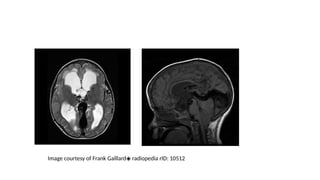

Vein of Galen aneurysmal malformation

• Common in childhood

• Commonest AV malformation diagnosed during antenatal screening

• Left to right shunt with high output cardiac failure

Imaging

• CTA

• MRI – signal void on T2

does not attenuate on flair

• MRA-Show dilated feeding and draining vessels

Image courtesy of Frank Gaillard radiopedia rID: 10512

Vein of Galenaneurysmal malformation • Common in childhood • Commonest AV malformation diagnosed during antenatal screening • Left to right shunt with high output cardiac failure

• 50.

Imaging • CTA • MRI– signal void on T2 does not attenuate on flair • MRA-Show dilated feeding and draining vessels

Image courtesy ofFrank Gaillard radiopedia rID: 10512 ◈

• #51 Selected images from an MRI demonstrate a markedly enlarge flow void centrally, just above the pineal region, draining posteriorly to the sagittal sinus.

• #52 Large vein of Galen aneurysm flow void with significant local mass effect: compression of the aqueduct and 3rd ventricle anteriorly with secondary hydrocephalus. The inferior sagittal sinus is draining into the aneurysm directly and straight sinus draining out (as seen on T1W sagittal imaging)